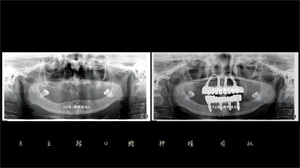

来院完成拍摄颌骨CT等常规检查操作后,张医生对其口腔情况做了初步评估后与王立超院长进行方案讨论。阿姨的牙槽骨情况确实不容乐观,给种植手术带来了极大的障碍,且必需过硬的医者技术来支撑完成。王院长经过仔细研究后,认为可以通过数字化技术模拟种植设计,并应用倾斜种植的方式避免复杂的植骨手术。

另一方面,我们在进行取模的过程中,发现彭阿姨很容易恶心干呕,采用传统取模的方式非常困难,所以决定利用数字化口扫取研究模,3D打印牙模。在克服种种阻碍因素后,由王立超带领的种植团队终制定出彭阿姨的种植方案——上下颌都采用All-on-4种植技术进行全口种植修复。在进行充分的沟通后,彭阿姨及其家人也同意了该方案。

这次的种植手术由王立超院长主导操刀,手术开始前,阿姨心情忐忑不安,王院长告诉她手术是无痛的而且我们已经做好充分的手术准备,不用紧张。终手术顺利完成,种植体成功植入牙槽骨内。All-on-4种植技术是一项精密的口腔种植技术,对医疗设备及医生技术的要求是极其严苛的。手术就是对术者的要求,因为有了王立超院长的精湛技术、良好的手术环境以及患者的全程配合,我们的种植团队才有十足的把握和信心,手术才得以顺利完成。